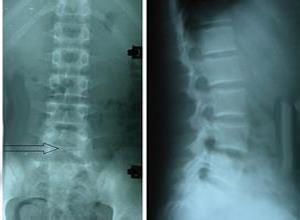

简介肌强直综合征(myotonic syndrome)是一组较为少见的遗传性疾病,包括先天性肌强直、萎缩性强直、先天性副肌强直等疾病,其共同的特点是:随意肌主动收缩后,或给予各种机械性刺激或电刺激后,出现肌肉的强直性收缩不能立即松弛,强直性收缩的肌肉僵硬,但不伴疼痛。寒冷,兴奋、忧虑、疲劳,发热等均可使肌强直加重,用叩诊锤叩击肌肉,可出现肌球。肌电图可出现强直电位。先天性肌强直综合征(congenital myotonia syndrome)又名Thomsen病,先天性肌强直症(myotonia congenita)、强直性肌营养不良综合征,Thomsen综合征等。